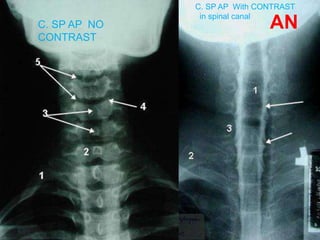

C. SP AP NO

CONTRAST

C. SP AP With CONTRAST

in spinal canal

Lumbar myelogram (AP, Lateral & both oblique

views)

1 = conus medullaris 2 = Cauda equina 3 = Left S1

nerve root 4 = Osteophyte

5 = epidural compression due to herniated L4-5 disk

7= Root sleeve